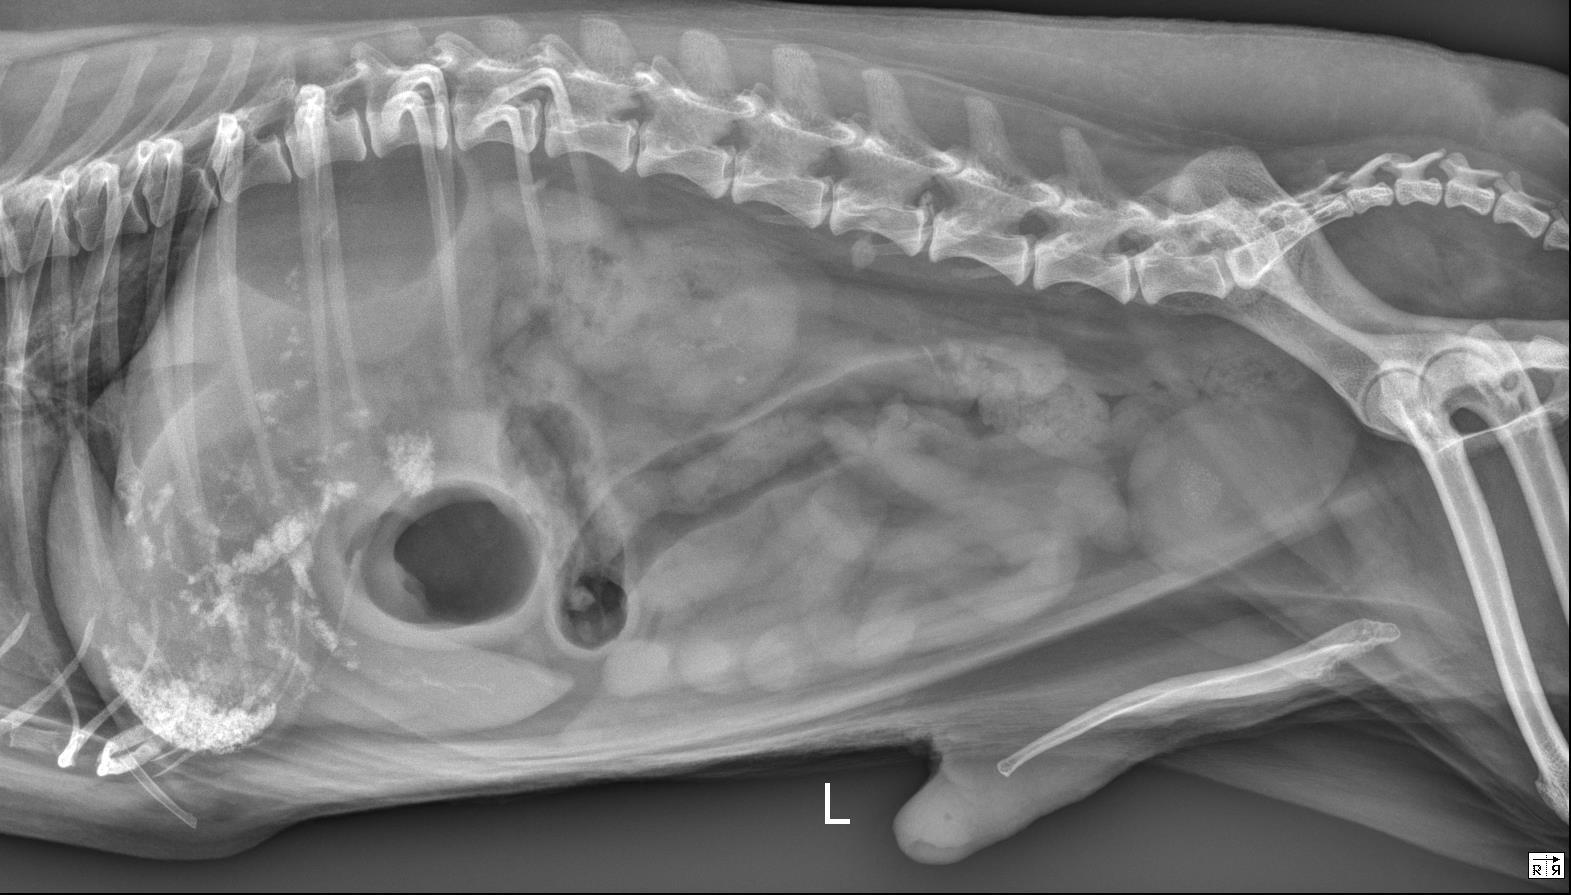

Abdomen - ventrodorsal and lateral radiographs are available for interpretation.

Abdominal serosal detail is normal.

There are numerous, stippled to angular, mineral opaque foci in the gallbladder and throughout the hepatic parenchyma which are suspected to be within the biliary tract, given the linear/arborized appearance. The liver is mildly enlarged with rounded margins extending beyond the costal arch. Best identified on the ventrodorsal radiograph, there is focal accumulation of this mineral superimposed with the proximal portion of the descending duodenum.

The stomach contains a small to moderate volume of gas and homogeneously soft tissue/fluid opaque material. The small intestines contain a small volume of homogeneously soft tissue/fluid opaque material and scant volumes of gas. The colon contains a small volume of heterogeneous fecal material and gas.

The kidneys have mildly undulant margins and contain multiple punctate to linear mineral opacities. There are numerous, small, well-marginated, round, faintly mineral opaque foci within the urinary bladder. The spleen is normal.

There is a small volume of mineral opaque material superimposed with multiple small intestinal segments on the ventrodorsal radiograph. On the lateral radiograph, this material is present superimposed with the retroperitoneal space at the level of the fourth lumbar vertebra.

Severe cholelithiasis and choledocholithiasis with suspected accumulation of mineral opaque material at the level of the duodenal papilla likely resulting in at least partial obstruction, given the reported clinical signs and labwork abnormalities. The planned abdominal ultrasound is recommended for further evaluation.

- Moderate hepatomegaly is non-specific, but likely represents a benign processes such as vacuolar degeneration or nodular hyperplasia. Malignancy (such as infiltrative round cell neoplasia) is considered less likely.

- Bilateral chronic renal degenerative changes and nephrolithiasis. Cystolithasis.

– The appearance of the gastrointestinal tract is most consistent with a non-specific gastroenteritis, given the reported vomiting.

– The mineral opaque material superimposed with the right caudal abdomen at the level of the fourth lumbar vertebra is suspected to represent mineralization of the extra-abdominal soft tissues.